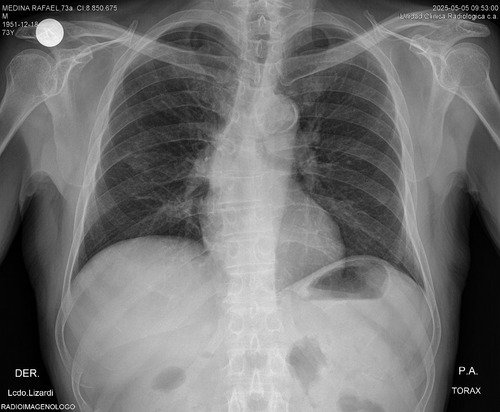

Atualmente, fui diagnosticado com um tumor no rim e parte do pulmão. Preciso de dinheiro para realizar um procedimento cirúrgico para retirar os órgãos afetados (um rim e parte do pulmão) e fazer os exames necessários para determinar se os tumores são cancerígenos.

Os procedimentos que preciso fazer são para extrair os tumores e realizar uma biópsia. Os procedimentos são um pouco complicados devido à minha idade e às complicações cardíacas que tenho.